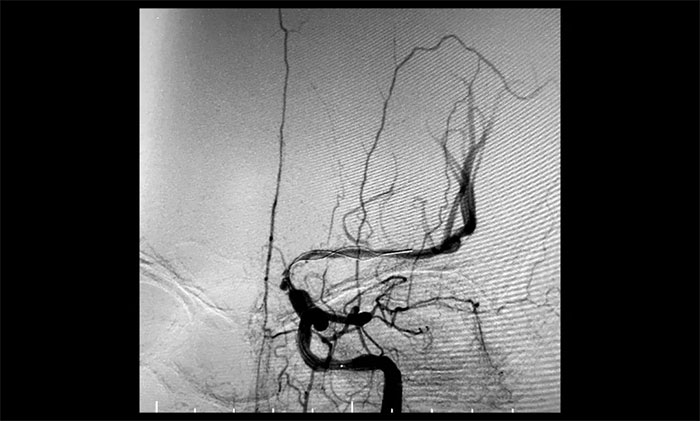

术后一个月,经过综合治疗,患者病情稳定。10月11日,再次行经皮左侧颈动脉慢性闭塞开通术,脑保护伞下左侧颈动脉支架置入手术,经皮左侧颈动脉球囊扩张成形术。术中造影显示,左颈内动脉起始段多发重度狭窄,左颈内动脉前向血流慢,左颈内动脉岩骨段中度狭窄,左颈内动脉眼动脉段、后交通段多发重度狭窄伴次全闭塞。

经微导丝成功进入狭窄、闭塞颈内动脉,在支架保护下,进行球囊逐段扩张,支架置入……,经多次球囊扩张,置入支架后,造影显示左颈内动脉起始段狭窄明显改善,左颈内动脉颅内段顺利再通,左颈内动脉眼动脉段、后交通段狭窄明显改善。造影及3D造影见左颈总动脉、左颈内动脉、左大脑中动脉显影可,行支架CT见颅内支架成形可,手术取得成功!

对于长节段颈动脉慢性闭塞再通,血栓逃逸是一个很重要的问题。由于患者左侧颈内动脉多处串联病变,闭塞段血栓负荷量大,保护伞无合适着陆位置,手术风险极大,难度极高。

术中,席刚明教授、王贵平博士采用COSIS技术,在保护伞无法到位的情况下,利用Syphonet®取栓支架作为颅内的远端保护装置,减少栓子逃逸,同时利用Syphonet®取栓支架的输送导丝完成微导管交换、球囊扩张、支架置入等操作,减少器械交换,降低并发症的发生。